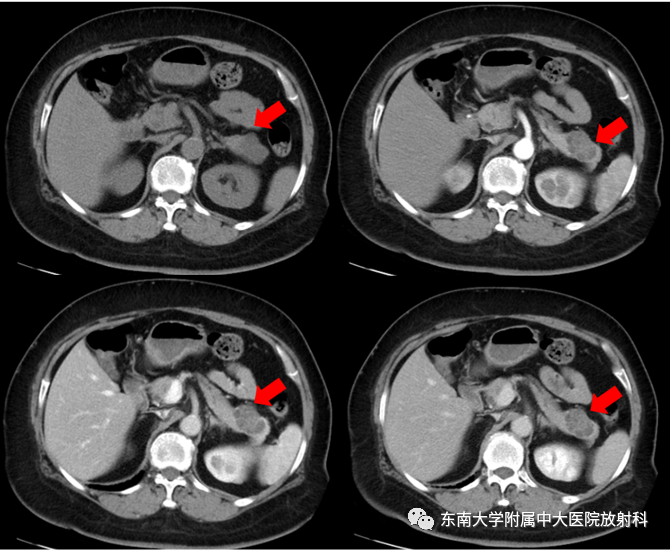

CT平扫+增强